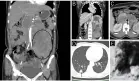

La radiografía de tórax muestra diferencia de altura vertebral anteroposterior.

La densitometría ósea se suspendió porque la radiografía de tórax permitió detectar el problema: fracturas por compresión osteoporóticas que habían pasado desapercibidas.

La radiografía lateral de tórax es una prueba de imagen infravalorada con frecuencia y disponible de manera generalizada para detectar la osteoporosis. A menudo muestra fracturas por compresión. No obstante, la evaluación de las radiografías por el radiólogo puede ser tan frecuente y rutinaria que a menudo pasan desapercibidos los hallazgos patológicos en la columna vertebral (visible también en la radiografía lateral).

Es importante que el médico realice una evaluación personal de la radiografía de tórax. Las fracturas por compresión se detectan con facilidad en una radiografía lateral de tórax y habitualmente indican la presencia de osteoporosis.